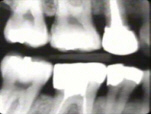

La Radiografía del lado derecho muestra pérdida moderada del hueso periodontal con una tendencia de bolsas infraóseas en los primeros premolares superiores. |

La radiografía del lado izquierdo revela pérdida moderada de hueso periodontal. |

La radiografía periapical muestra al cuadrante superior derecho, en particular al premolar, una bolsa infraósea en mesial y distal |